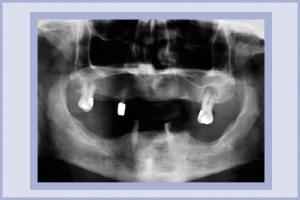

Paziente di sesso maschile, di anni 60, che non riferisce patologie degne di nota. Presenza di tre elementi all’arcata superiore di cui uno in regione mascellare sinistra con reazione periapicale e due elementi all’arcata inferiore (Fig. 1).

- Fig. 1 – RX pretrattamento